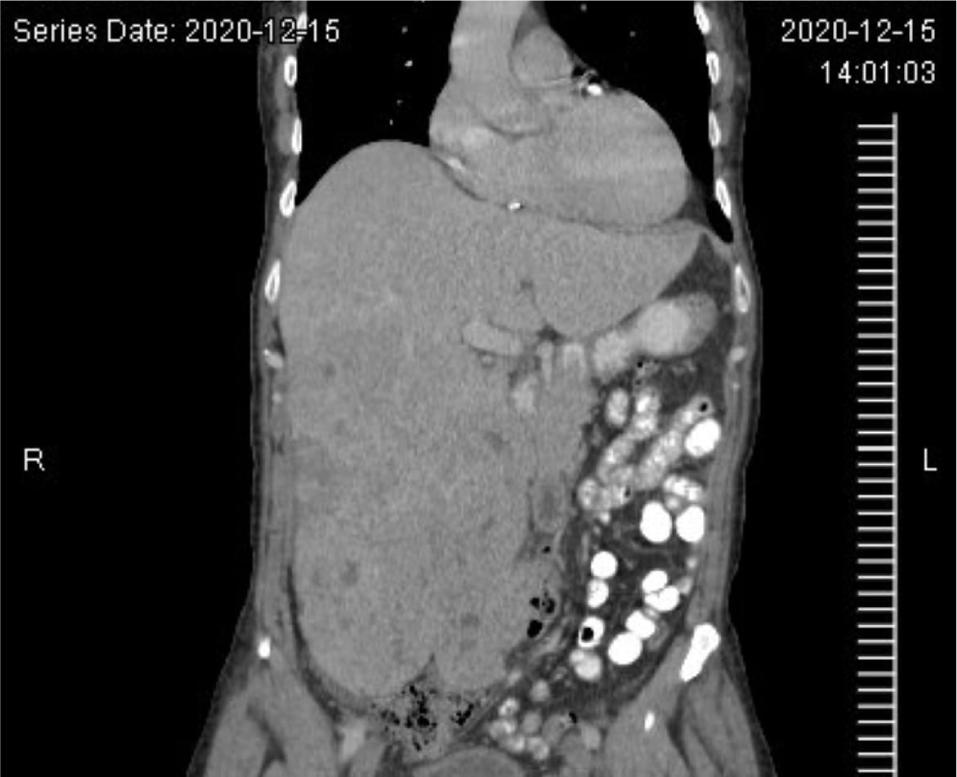

A 57-year-old man presented to his pulmonologist with worsening headaches and sinus congestion. This ultimately prompted computed tomography (CT) imaging which revealed a small left lung effusion, two nodules of the right lung, left hemidiaphragmatic elevation, and a 20-cm centrally necrotic neoplasm in the left upper quadrant (Figure 1). Positron emission tomography (PET) re-demonstrated the retroperitoneal mass, measuring 30 × 16 × 11 cm with a standardized uptake value (SUV) of 7.0, suggestive of malignancy. One fine-needle aspiration (FNA) sample and four core needle biopsy samples were obtained, revealing a malignant PEComa. Magnetic Resonance Imaging (MRI) demonstrated no brain metastases. However, further axial imaging revealed pelvic adenopathy and multiple pulmonary nodules, indicative of metastatic disease.

Figure 1: Abdominal CT images with contrast. CT images of the abdomen in coronal (A) and axial (B) planes with contrast enhancement demonstrating a large left retroperitoneal mass.